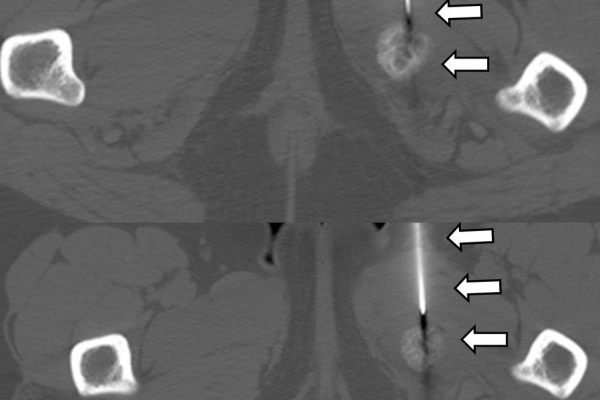

Οι κατευθυνόμενες εγχύσεις σε αθλητικές κακώσειςαποσκοπούν στη μείωση του πόνου, την ενίσχυση της αποτελεσματικότητας της φυσικοθεραπείας και την επιτάχυνση της διαδικασίας επούλωσης για την πιο γρήγορη επάνοδο του αθλητή στις αθλητικές του δραστηριότητες. Η πιο διαδεδομένη έγχυση αποτελεί η έγχυση PRP.Ανήκει σε μια σύγχρονη θεραπευτική μέθοδο γνωστή ως Ορθοβιολογική θεραπεία και βασίζεται την ικανότητα του οργανισμού να θεραπεύεται με τα δικά του αποκλειστικά θεραπευτικά μέσα χωρίς να υπάρξει χρήση φαρμάκων.Το PRP (Platelet Rich Plasma)-πλάσμα πλούσιο σε αιμοπετάλια- σήμερα αποτελεί μια θεραπευτική μέθοδο πρώτης γραμμής με σχετικά μεγάλη επιτυχία για την επούλωση τραυματισμένων τενόντων, μυών και εκφυλιστικών παθησεων όπως οστεοαρθρίτιδα.Η εφαρμογή του περιλαμβάνει μία ευρεία ποικιλία από παθήσεις όπως:

- Μυικές θλάσεις (οξείες και χρόνιες)